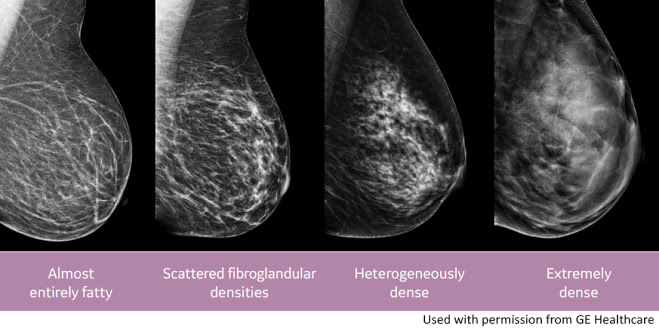

The 1st World Conference of Breast Ultrasound in Philadelphia (1979) recognized ultrasound superiority in dense breast diagnostics but the density level was never quantified until recently. Mammography assessment of breast density is graded into four categories. Mammographers readily admit that these levels are subjective at best and technical factors such as mammary tissue compression and x-ray voltage/amperage dramatically influence the darkness or whiteness of the image

A mammogram shows how dense your breasts are. When you get the results of your mammogram, you may also be told if your breasts have low or high density. Women with dense breasts have a higher risk of getting breast cancer.

BREAST CANCER RISK: Women with dense breasts have a higher chance of getting breast cancer. The more dense your breasts are, the higher your risk. Scientists don’t know for sure why this is true. Breast cancer patients who have dense breasts are not more likely to die from breast cancer than patients with non-dense (fatty) breasts.